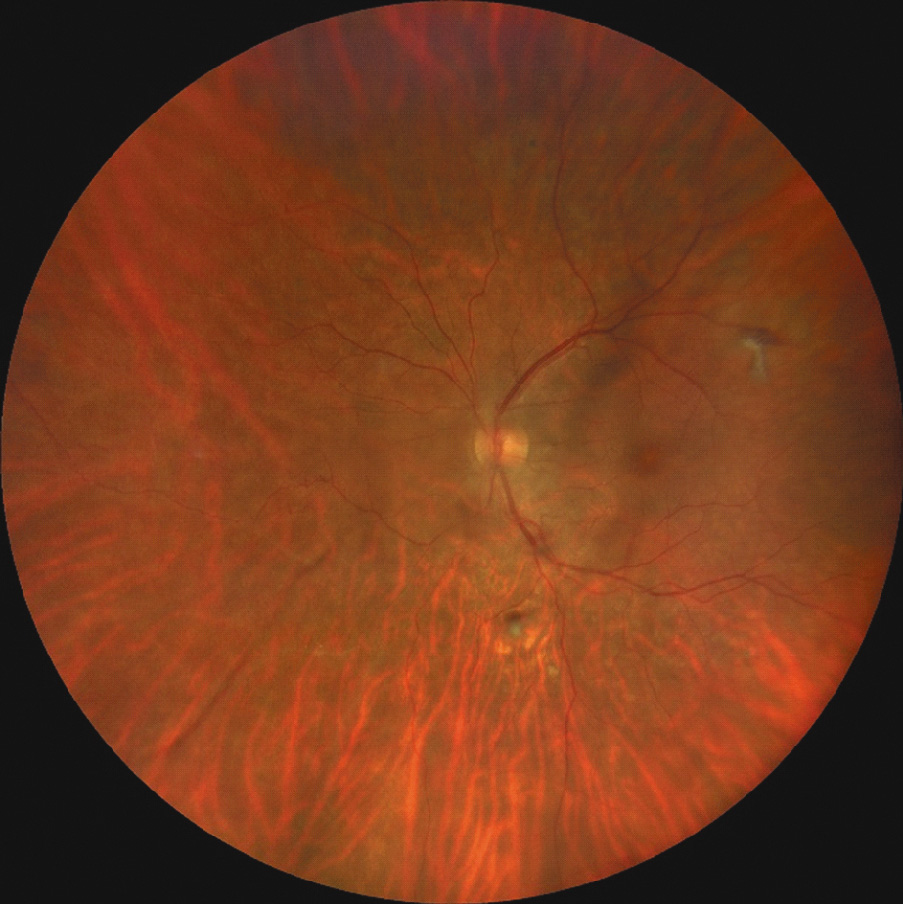

Status oculorum OU: при биомикроскопии передний отрезок и придаточный аппарат обоих глаз без особенностей. В стекловидном теле частичный организовавшийся гемофтальм. На глазном дне: диск зрительного нерва бледно-розовый, границы четкие, артерии сужены, вены расширены, в просвете верхней ветви центральной вены сетчатки и ее ветвей второго порядка желтые, блестящие кристаллические эмболы и следующие за ними запустевшие сосуды, ишемизированные зоны сетчатки и очаги нео- васкуляризации, на периферии сетчатки следы лазерных коагулятов, в макулярной зоне левого глаза – рефлекс стушеван, макулярный отек (рисунки 1, 2).

Рисунок 1. Фото глазного дна правого глаза.

Офтальмоскопическая картина, а именно двусторонние кристаллические эмболы и следующие за ними запустевшие сосуды, позволила судить об окклюзионной этиологии изменений на глазном дне. Мы предположили, что белый материал в сетчатке обоих глаз представляет собой тальк. В ходе углубленного сбора анамнеза пациент признался во внутривенном употреблении толченых наркотических препаратов в течение 10 лет.

Клинические проявления ТР развиваются в результате длительного накопления мелких частиц талька в сосудах сетчатки. На глазном дне обнаруживаются точечные бело-желтые кристаллы в макулярной области, а также по ходу сосудистых аркад [7]. Длительная эмболизация частицами талька вызывает недостаточную перфузию и, как следствие, ишемию сетчатки и активацию процессов неоваскуляризации [2, 7–10].